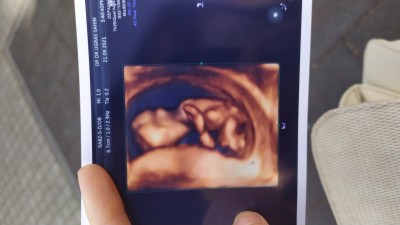

İlk 12 haftalıkken kız dedi doktorum. İkinci kez erkek dedi ama kesin deil dedi . Şuan 16+4 haftaligim bugünde gittim kesin bişey demedi bebeğim bacak arasını kapatıyor göstermiyor .

Gebelik haftası 16+4